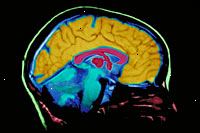

(MRI skenování páteře, MRI skenování mozku)

Magnetická rezonance (MRI) je diagnostická metoda, která používá kombinaci velkého magnetu, rádiových kmitočtů, a počítač produkovat detailní snímky z orgánů a struktur v těle.

Stroj MRI je velký, válcovitý (ve tvaru trubice), stroj, který vytváří silné magnetické pole kolem pacienta. Toto magnetické pole, spolu s radiofrekvence, mění přirozené uspořádání atomů vodíku "v těle. Počítače jsou pak použity k vytvoření dvojrozměrné (2D) obraz struktury těla nebo orgánu, na základě aktivity vodíkových atomů. Cross-řezy lze získat odhalit další podrobnosti. MRI nevyužívá ionizující záření, stejně jako rentgenové záření nebo počítačová tomografie (CT).

Magnetické pole je vytvořeno a impulsy z radiových vln jsou odesílány ze skeneru. Magnetické pole zarovná vodíkové protony ve vašem těle po stejném vektoru. Rádiové vlny pak srazit částice z této vyrovnané poloze. Vzhledem k tomu, jádra přestavět zpět do správné polohy, jádra vyslat rádiové signály. Tyto signály jsou přijímány prostřednictvím počítače, který analyzuje a převádí je do obrazu té části těla zkoumáno. Tento obrázek na sledování monitoru se objeví. Některé stroje MRI vypadat úzkých tunelech, zatímco jiní jsou více otevřené.

Magnetická rezonance (MRI) mohou být použity namísto výpočetní tomografie (CT) v případech, kdy orgány nebo měkké tkáně jsou studovány, protože s MRI skenování kostí nezakrývají obrazy orgánů a měkkých tkání, stejně jako CT skenování.